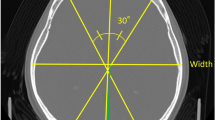

We report the case of a Japanese girl with a severe type of Moebius syndrome. Her morphological features were a mask-like face, limitation of horizontal eye movements, severe bulbar palsy, multiple and bilateral arthrogryposis including the elbow, knee, and ankle joints, and clubfeet. After birth, her general condition became worse because of repeated apneic spells and aspiration pneumonias due to dysphagia. She finally required tracheotomy. Computed tomography (CT) of the brain revealed minute calcifications on the fourth ventricle floor; this may have been due to severe damage to the brain stem. It is most likely that the various manifestations in our patient were due to disturbance of the blood supply to arteries perfusing the brain stem and to some other arteries, at a critical stage of fetal development.